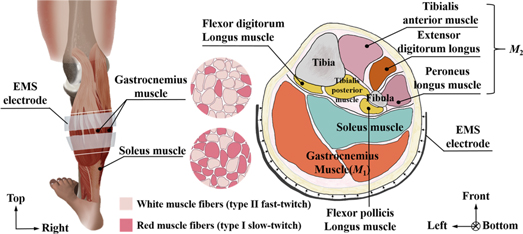

Figure 9 shows the human calf muscle structure and cross-sectional image. From this figure, M1 is recognized as the position of the gastrocnemius muscle. From a previous electromyography study, the gastrocnemius muscle is recognized to be primarily involved in the fast movements of the leg as it is dominated by white muscle fibers (Mademli and Arampatzis 2005). Therefore, the conductivity 〈σpost 〉M1 in M1 is increased in the post-training by gastrocnemius muscle contraction.

Figure 9. Human calf muscle structure and cross-sectional image.

Standard image High-resolution imageMoreover, M2 is recognized as the position of the tibialis anterior muscle, extensor digitorum longus muscle, and peroneus longus muscle. From the viewpoint of muscle structure, these muscles in M2 on the front calf side are stretched while the gastrocnemius muscle is contracted because those muscles of M1 and M2 work together to make the tiptoe movement. The muscles in M2 are also trained simultaneously even though M2 is not covered by EMS while the gastrocnemius muscle is repeatedly contracted under EMS. Therefore, the spatial-mean conductivity 〈σpost 〉M2 in M2 is also increased in the post-training part.

Secondly, why soleus muscles are not responded by EMS is discussed even though the posterior calf muscles are mainly composed of gastrocnemius muscles and soleus muscles. From figure 9, the soleus muscles located behind the gastrocnemius (farther from the skin) have more red muscle fibers, and are the primary active muscles in a standing posture. While EMS is applied to human calf muscles, the stimulation current does not cause soleus muscle contraction in a short time. In addition, a more recent study has shown that EMS only indiscriminately stimulates the most superficial muscle fibers under the electrodes (Gregory and Bickel 2005). The soleus muscles is located behind the gastrocnemius (farther from the skin). In short, the deep soleus muscle cannot be stimulated by EMS. Therefore, the conductivity in the soleus muscle position is not changed in the post-training part.